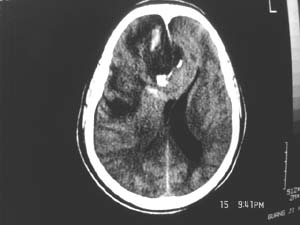

女,60岁,反复头痛3天,呕吐3小时伴昏迷10分钟入院检查。

右额叶占位,有占位效应,中线偏移,病灶位于镰旁,呈囊实性并有钙化,

考虑:1.脑膜瘤。2.胶质瘤。

理由:1.病灶位于前颅凹及镰旁,有明显占位效应---支持脑膜瘤。

2.病灶呈囊实质性并有条状钙化,符合胶质瘤改变;

另外也不排除包虫病的可能。

右额叶占位,有占位效应,中线偏移,病灶位于镰旁,呈囊实性并有钙化 kaolv  少枝胶质瘤。胶质瘤。

病变范围较大,累及左额叶,内见钙化。及高密度灶。考虑;胶母伴卒中可能大。